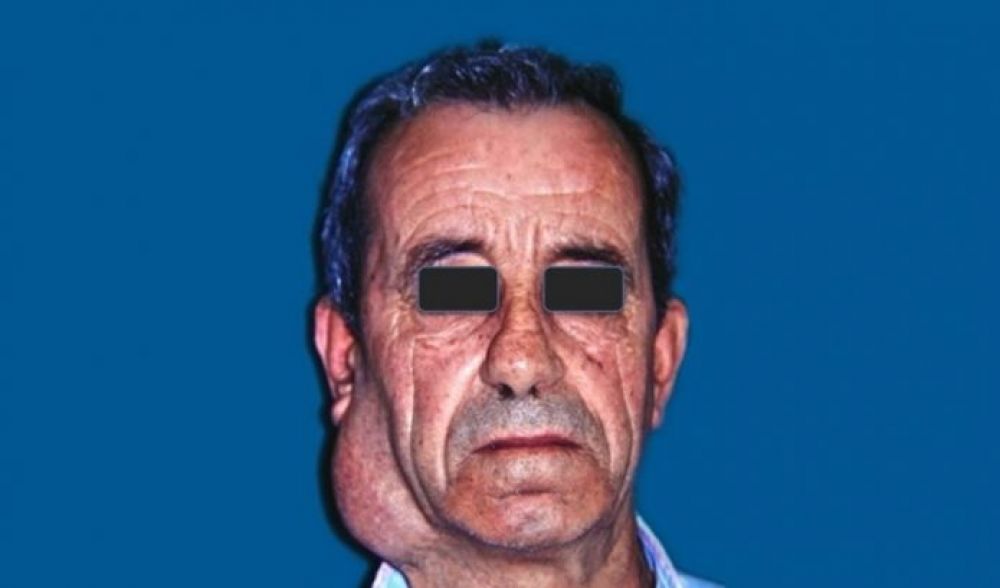

Tanto las mayores como las menores pueden ser el asiento de diversas lesiones tumorales, infecciosas, traumáticas… etc. que pueden requerir procedimientos quirúrgicos para su tratamiento.